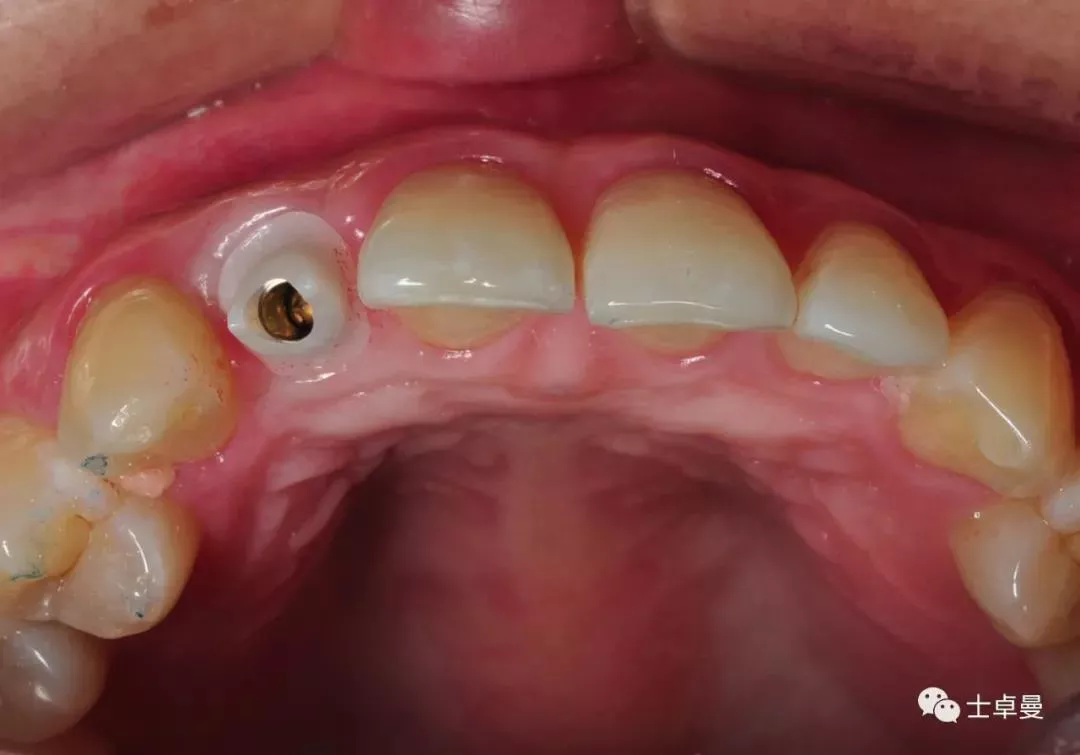

术前口内照

断根舌侧劈裂至龈下3mm-4mm

·        唇侧龈缘曲线完好,与邻牙协调,牙龈质地健康,无炎症,薄龈型;

临时义齿口内就位

·        根尖片显示临时基台就位良好,无骨阻挡;